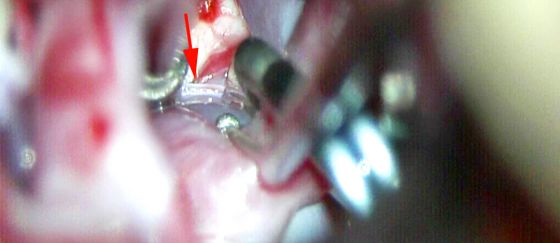

图13:左侧经侧裂入路显露一个基底动脉分叉部动脉瘤(显示Liliequist膜与PCoA起始处(箭头))(第一排)。通过Liliequist膜找到PCoA,将动眼神经从蛛网膜附着带上松解(第二排)。轻柔推移PCoA的丘脑穿支血管,安全地从近端控制基底动脉(第三排)。直形永久夹放置到瘤颈后,立刻用固定牵开器牵拉颞叶(第四排)。仔细探查发现对侧P1段起始处及相关的穿支保留完好。动态牵拉使皮质的损伤最小(下排)。

注:ICA:颈内动脉。